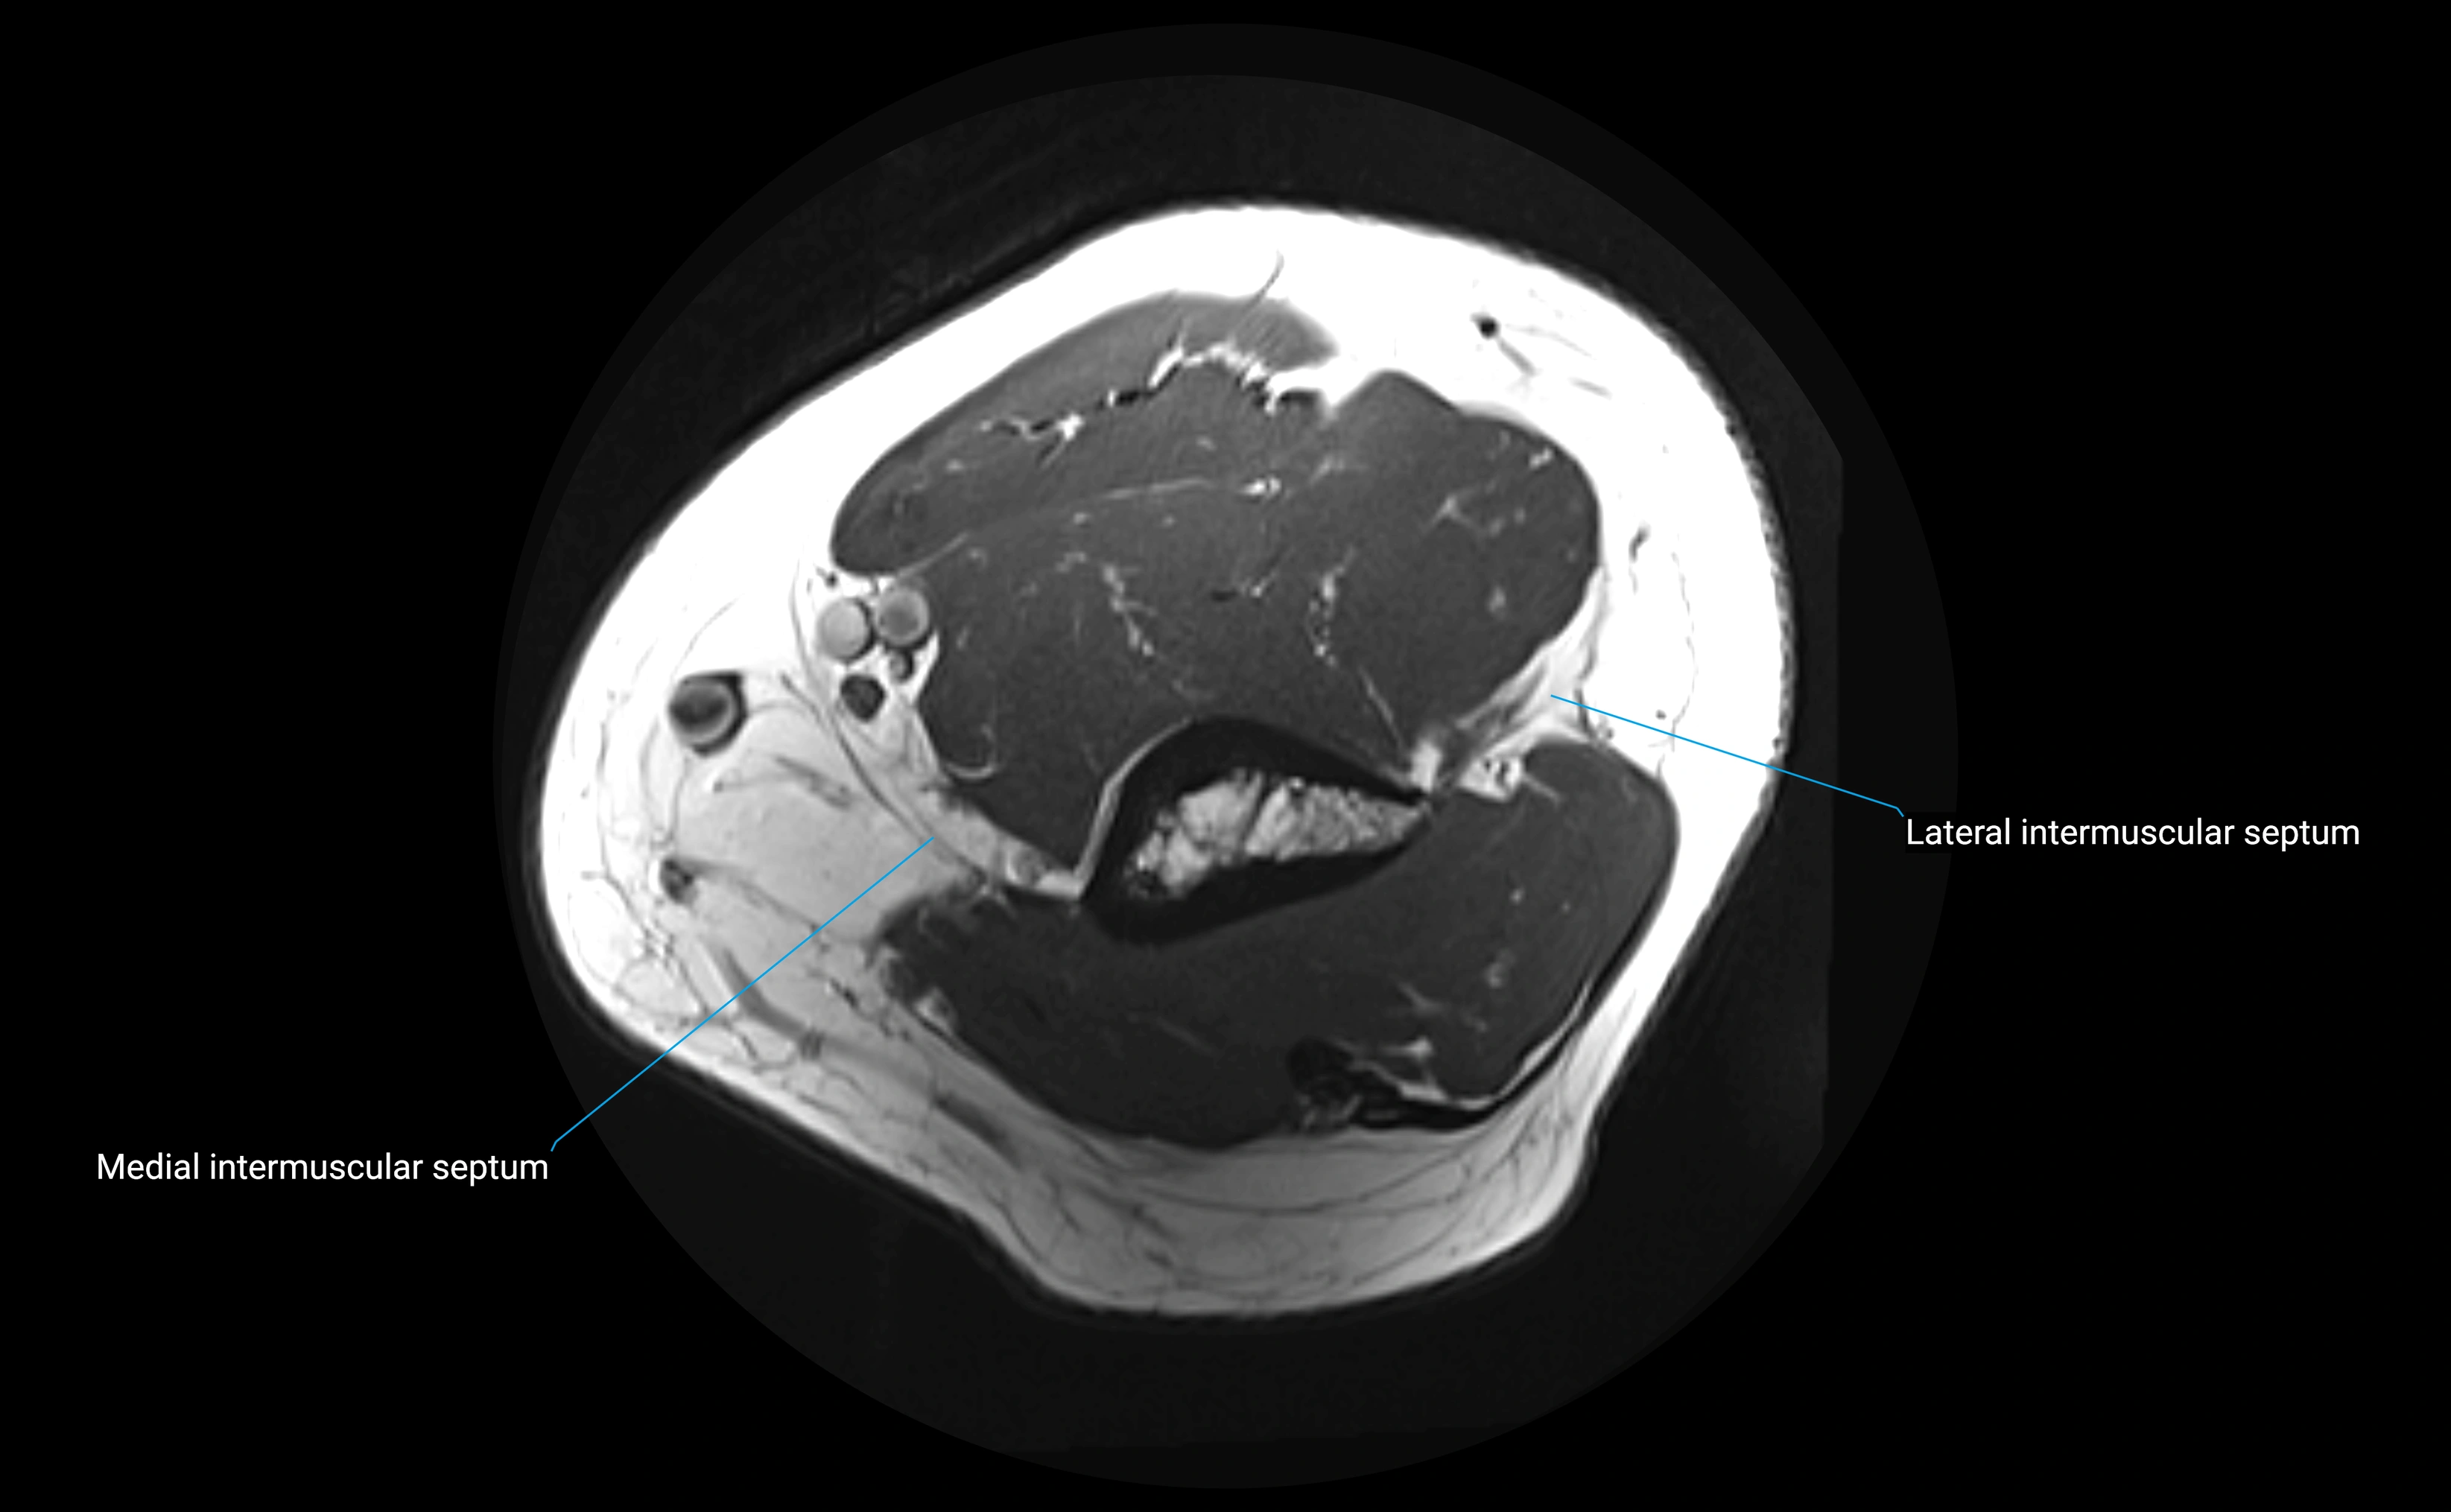

MRI images

image